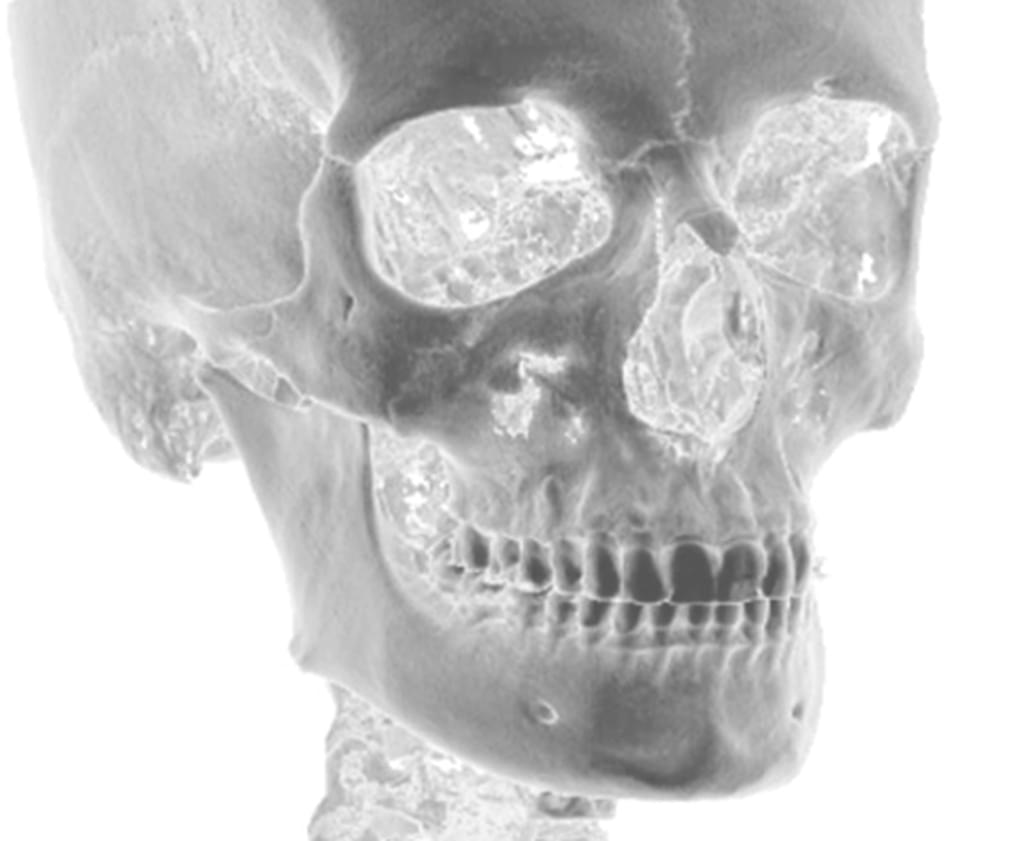

Výpočetní tomografie

(3d čelisťové snímky a snímky ústní dutiny)

CBCT Maxilofaciální diagnostika